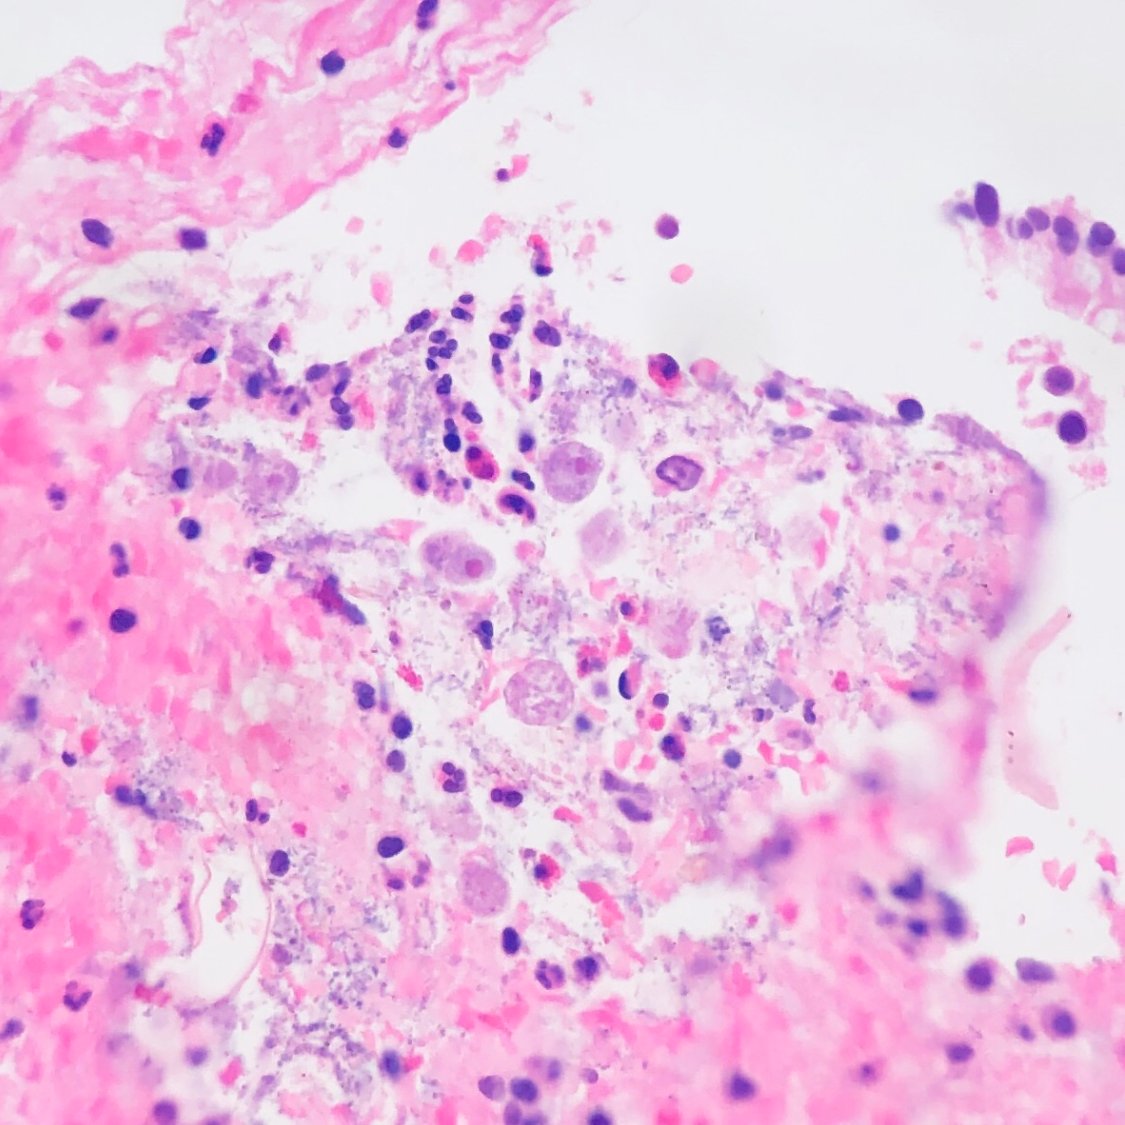

Soft tissue nodule. Coccidioides within a multinucleated cell.

#idpath pic.twitter.com/nAjn9HV2fe